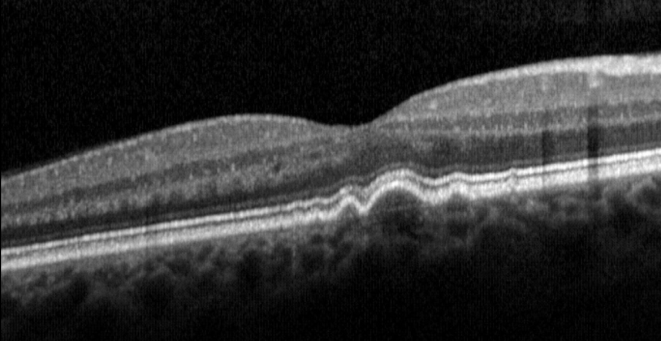

Рисунок » Друзы в макулярной области при сухой форме возрастной макулярной дегенерации сетчатки»